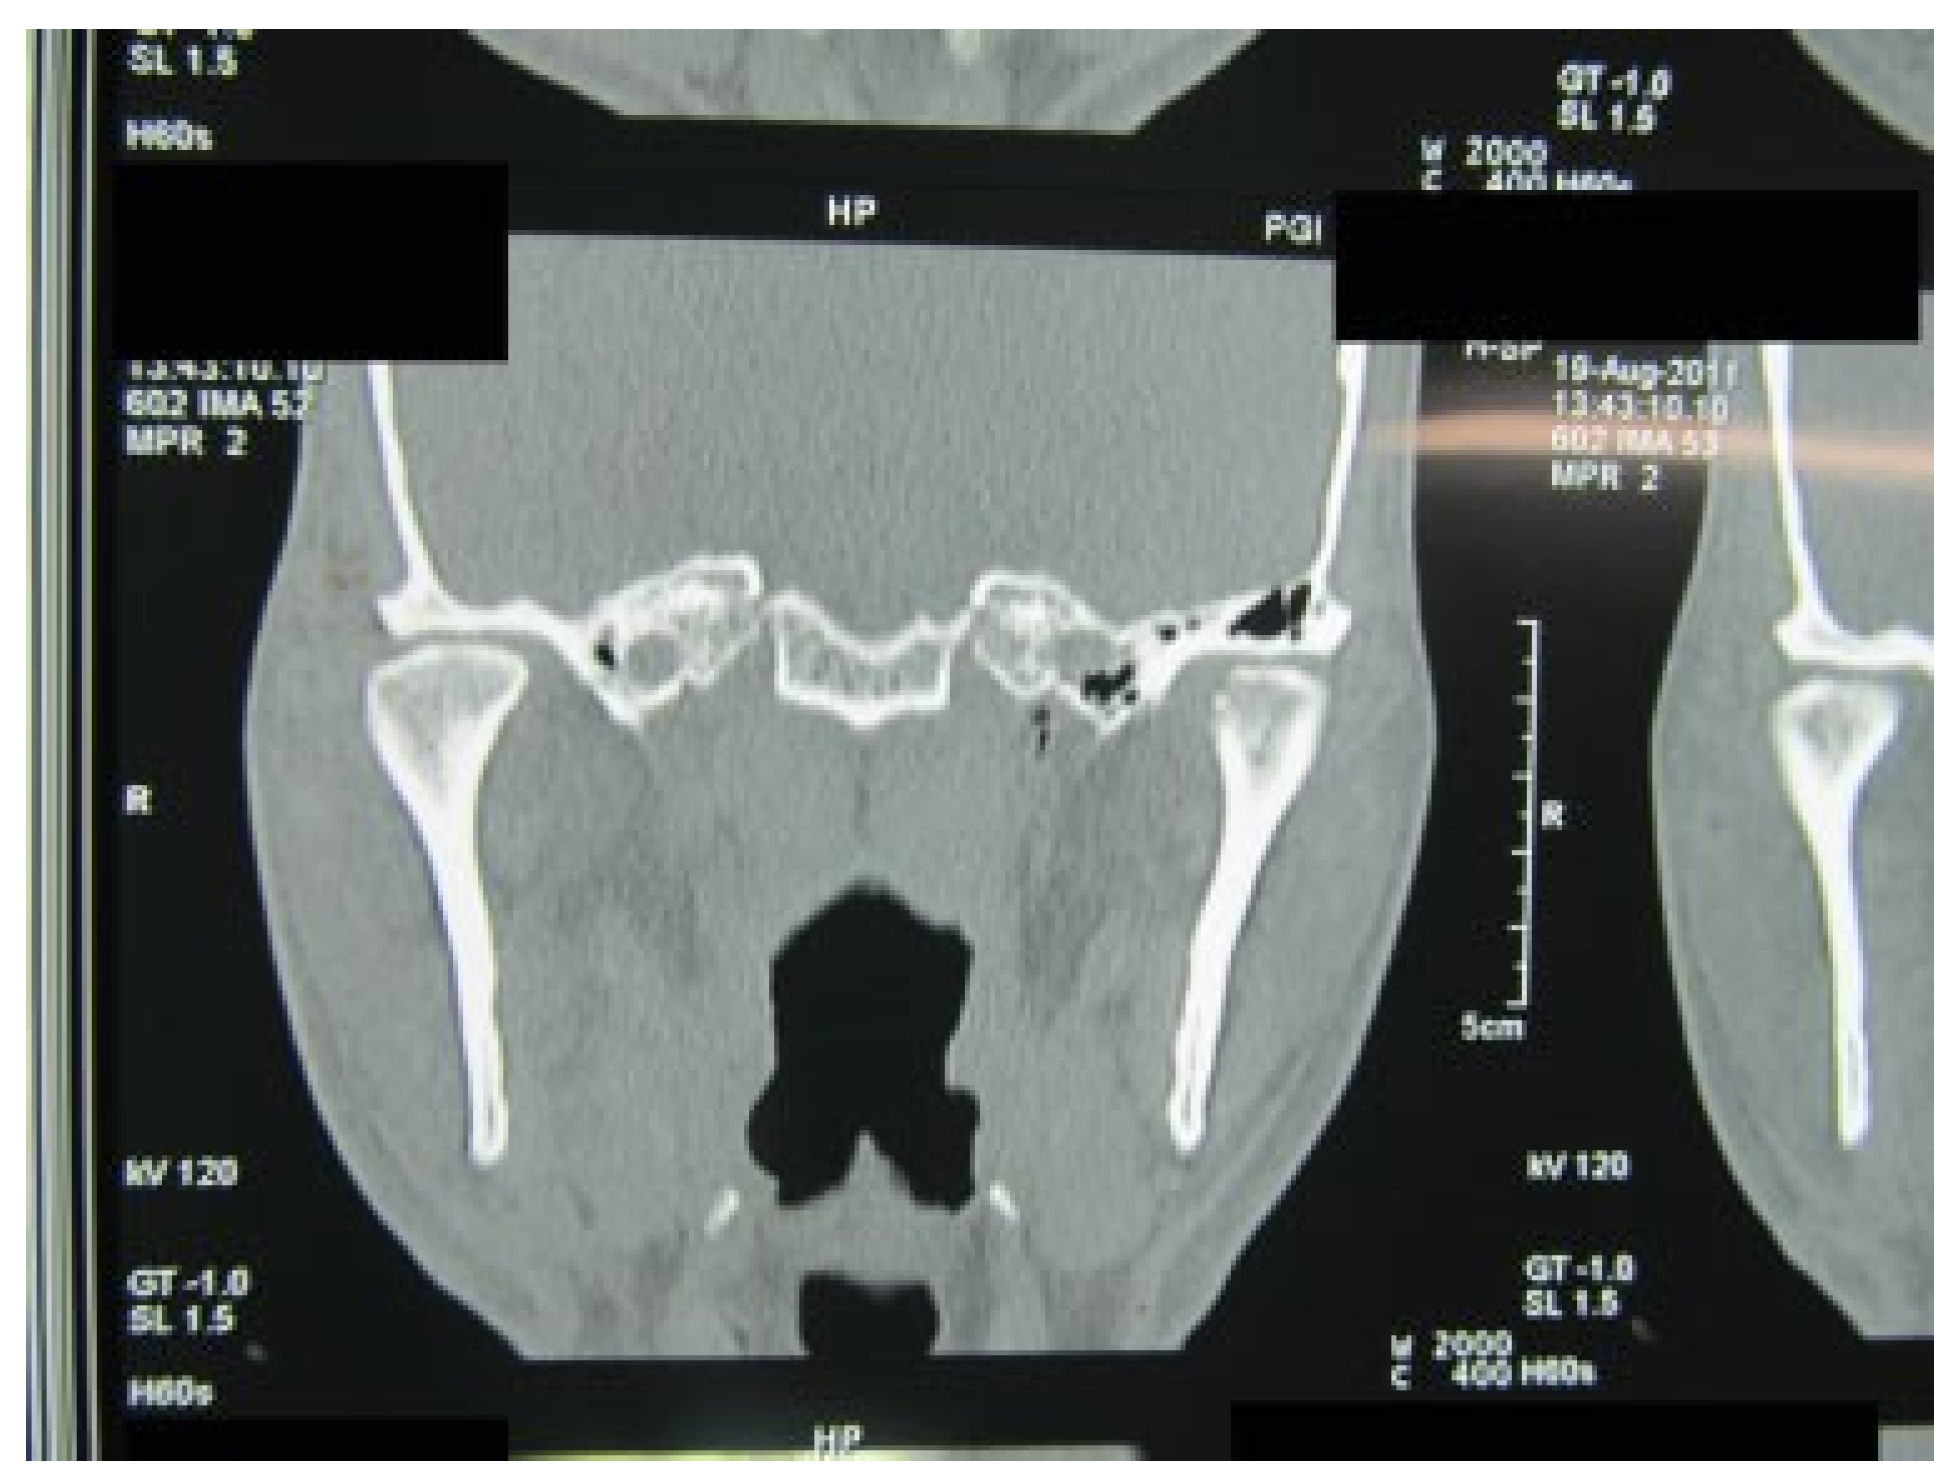

:1. Case Report